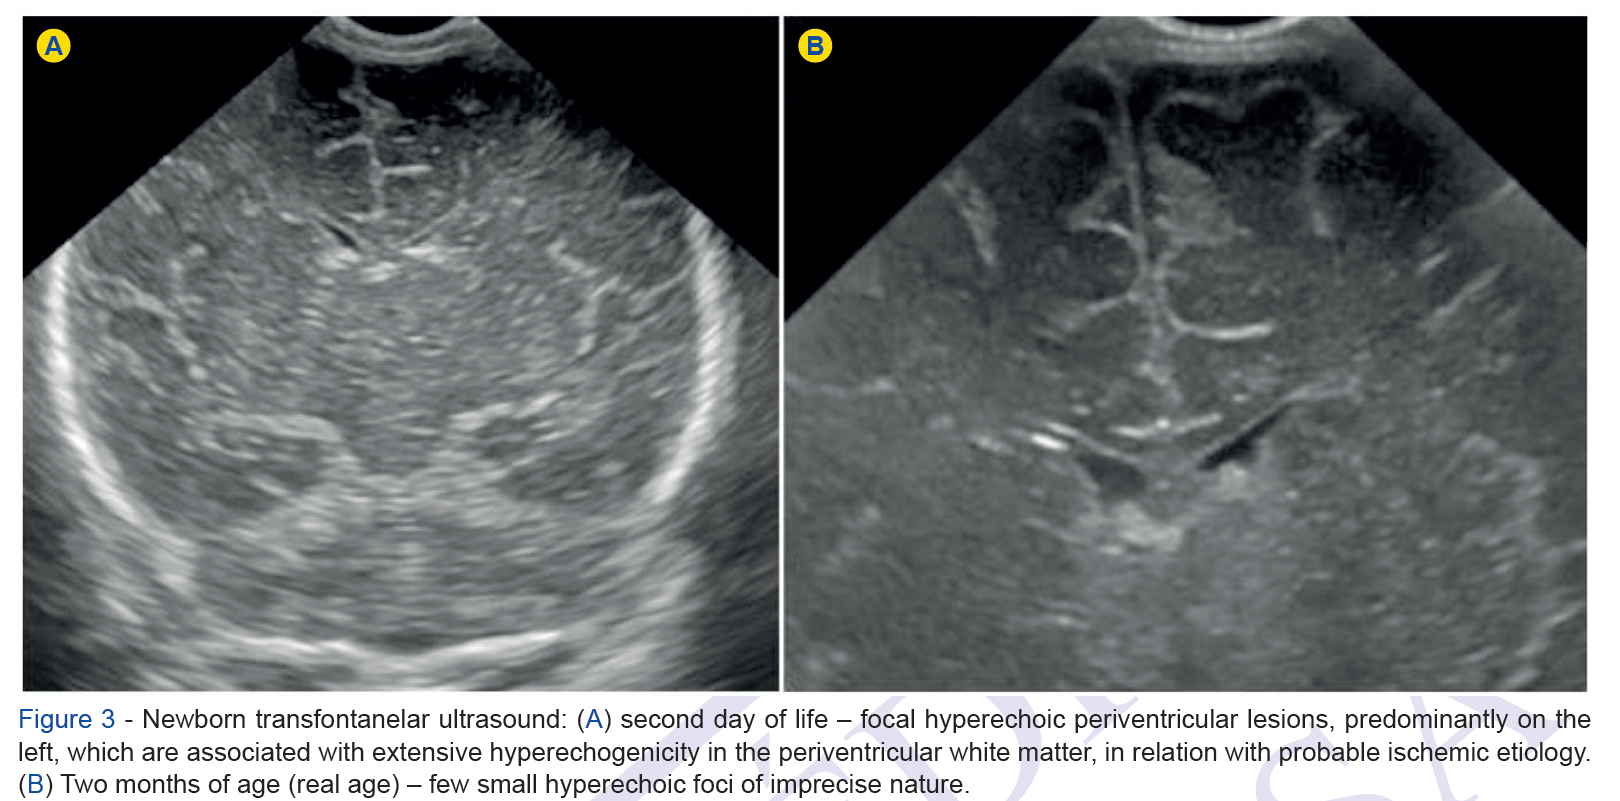

The incidence of single fetal death in twin pregnancy varies from 0.5% - 6.8%, leaving the surviving fetus with increased morbi-mortality.

The prognosis is wors...